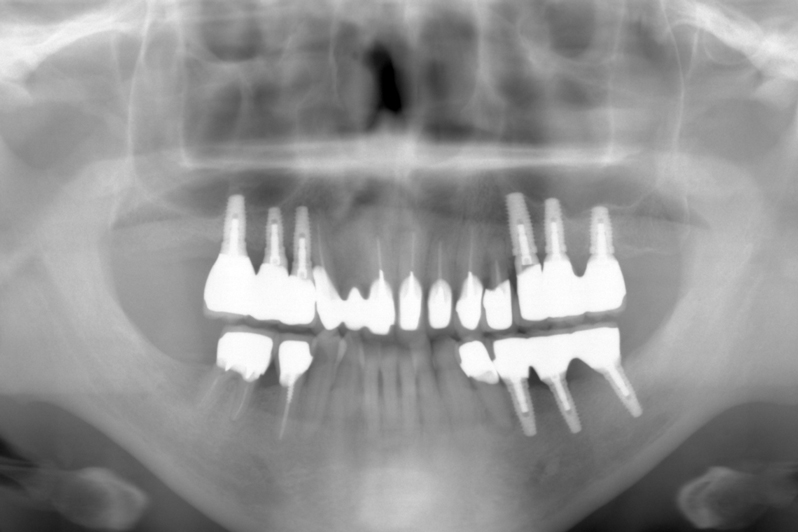

受傷時パノラマレントゲン(2018年5月17日)

【受傷時 パノラマレントゲン】